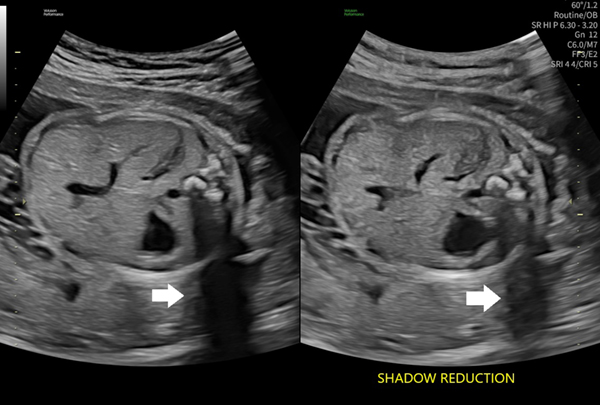

診断の安心につながる,高画質

画像調整を簡素化する機能を搭載し,迅速かつ確実な診断をサポートする。画質をワンボタンで最適化することで,より正確な診断に貢献する。

音響陰影を補うShadow Reductionの比較(左 off/右 on)